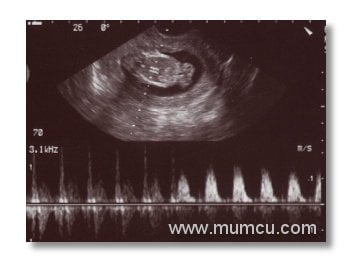

12 haftalık gebelikte bebeğin kalp atımlarının M Mode ve Doppler ile izlenmesi

Vajinal ultrasonografi